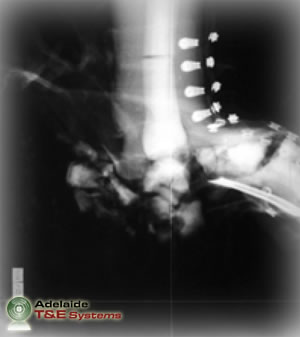

The principal method of injury assessment is standard medical examination, both physically and radiographically, to diagnose outcomes that often include dislocations, fractures and traumatic amputations.

The flash x-ray images above show the FSLLM’s response in millisecond intervals to 50g of plastic explosive buried 20mm below sand with 50mm of standoff. Note: images sourced from DSTO-TR-1829.